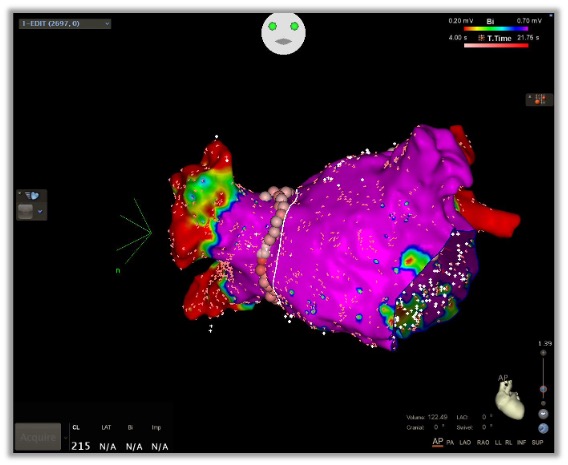

A procedure that uses energy to destroy abnormal heart tissue causing irregular rhythms.